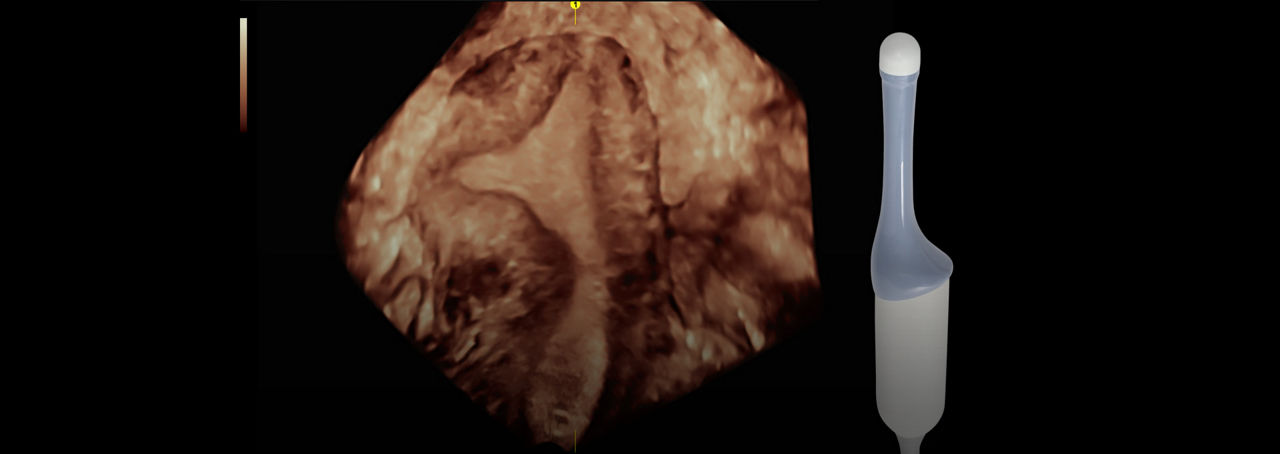

Uterine Trace

Incorporating 3D into your practice is easier than ever with Uterine Trace. From a standard view, simply trace the endometrium and the system automatically acquires a volume and then exacts the critical coronal view.